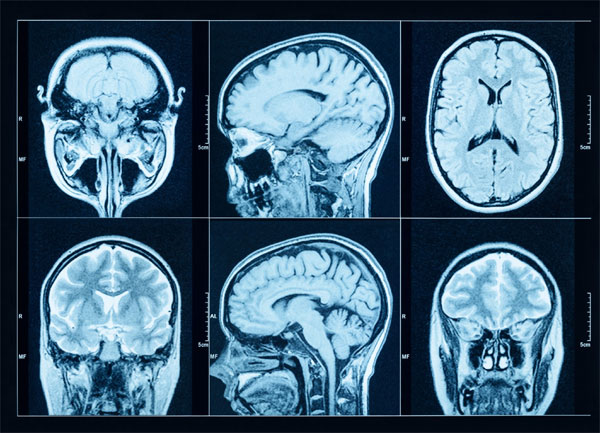

Using a pioneering imaging method called ASA-PD (Advanced Sensing of Aggregates for Parkinson’s Disease), researchers successfully identified and analysed microscopic protein clusters known as alpha-synuclein oligomers. These clusters are widely believed to play a key role in the onset and progression of Parkinson’s but have, until now, remained undetectable in actual human brain tissue due to their minuscule size.

The breakthrough came through the combination of ultra-sensitive fluorescence microscopy and ASA-PD, which together amplify the weak signal of oligomers while minimising background noise. This allowed the researchers to detect millions of individual oligomers in post-mortem brain samples.